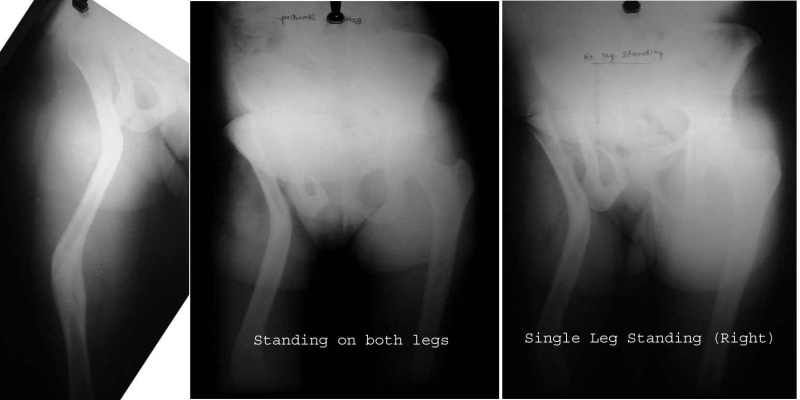

Attached are some pics of a case of an 18 year old girl with shortening and trendelenburg lurch, both of which were corrected by the procedure.

The xrays in single stance show that the pelvis continues to remain level, in the single stance, despite the absence of the head.